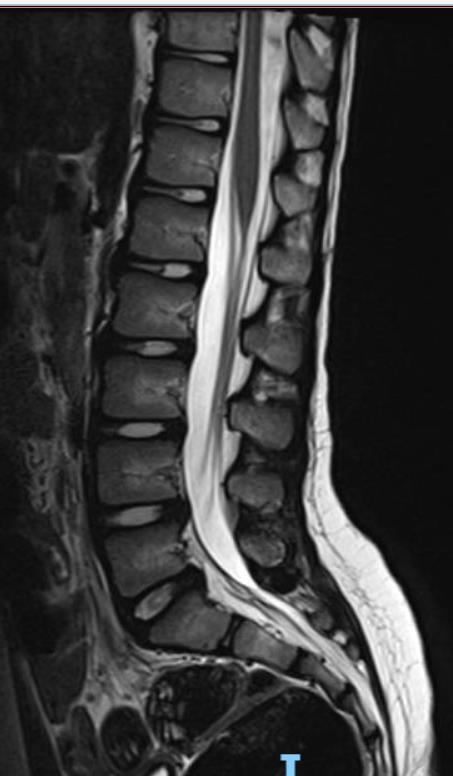

Adductor Longus L2, L3

Vastus Lateralis L3,L4

Tibialis Anterior L4, L5

Peroneus longus L5, S1

Gastrocnemius S1, S2

Abductor hallucis S1, S2

Sphincter S2